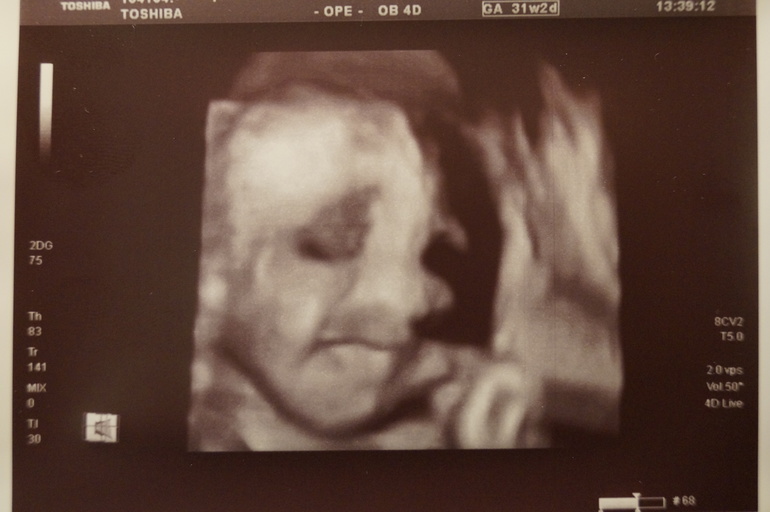

Дальше наша милашка!

Дочка у нас будет жизнерадостной и весёлой! Врач опять смогла запечатлеть нашу очаровательную улыбочку!!!!